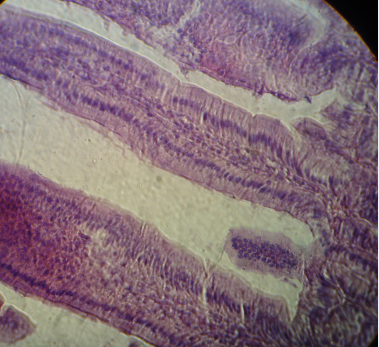

Histology of the intestinal mucosa of mice fed with hydrolyzed rice formula

The appearance of the intestinal mucosa of mice fed with hydrolyzed rice formula indicates an improvement in the structure of the intestinal mucosa compared to the positive control groups. The villi are increasingly thin and long, limited by a simple cylindrical epithelium, formed with high striated cells with regular basal nuclei that corresponds to the enterocytes (Figure 6, Figure 7).

The lamina propria appears fibrous and polymorphic with various mononuclear elements which correspond to the immune system cells (lymphocytes). The villous height indicates a highly significant difference compared with the positive control groups.

Fig. 7: Microscopic observation G (10 x 40) of intestinal biopsy of mouse immunized with α-La then fed with hydrolyzed rice formula for 28 days.

The villi are increasingly thin and long, bordered by a simple cylindrical epithelium, which is formed with high striated cells corresponding to enterocytes.